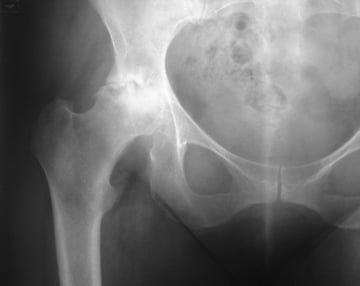

An arthritic hip.  The smooth round ball has been eroded and it is rubbing in the socket

The process of arthritis in the hip is a destruction of the articular cartilage surface of the joint.  This can occur because of childhood abnormalities in the hip caused by unusual types of hip disease or by the development of a very shallow socket in the hip.  These abnormally shaped hips tend to wear out in adult life.  The cartilage can also be damaged by arthritis.  There are two main types of arthritis which affect the hip.